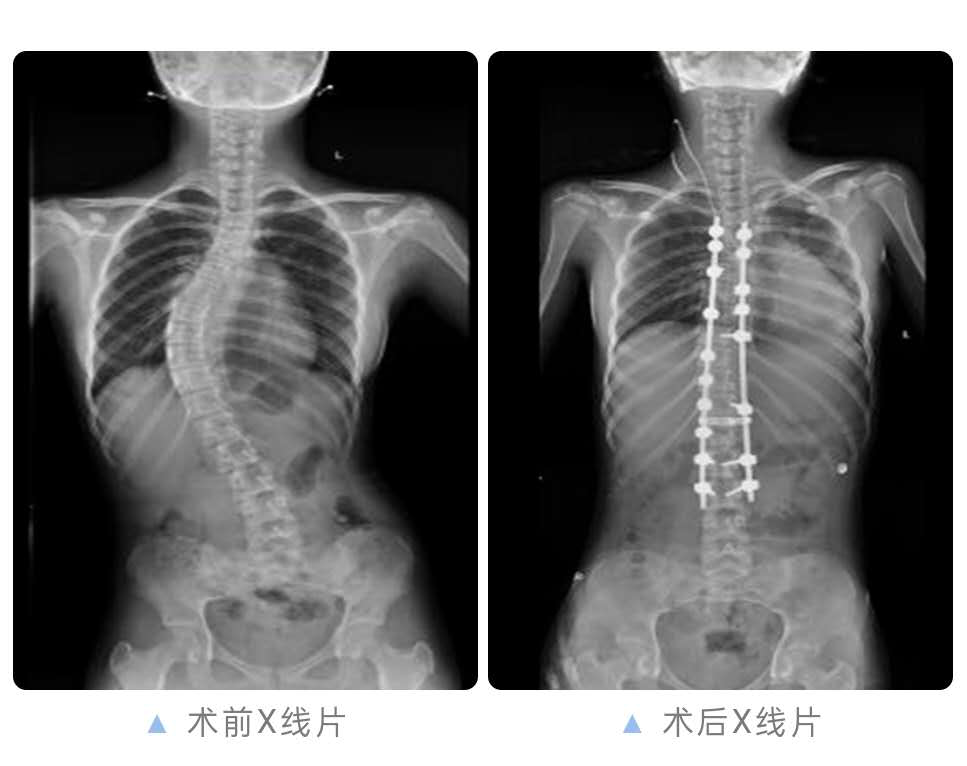

通过检查发现,小沈的脊柱侧弯畸形明显,已大于40度,心肺因受压迫导致心肺功能降低,矫正的难度很大、风险高,一不小心就可能因为脊髓损伤导致瘫痪或刺破大血管危及生命。

在广医五院骨科专家李健教授的指导和麻醉科、手术室、神经外科等多学科的大力配合下,成功的为小沈进行了“后入路胸腰椎多节段椎弓根螺钉内固定、侧弯矫形+髂骨取骨、异体骨植骨融合术”,这也是广医五院完成的第一例儿童脊柱侧弯矫形手术。

在医护人员的精心护理下,术后,小沈在外观上两侧肩膀高低不等畸形明显改善,X线片显示脊柱侧弯完全得以矫正,所担心的并发症无一发生,目前已顺利出院,回归正常生活。